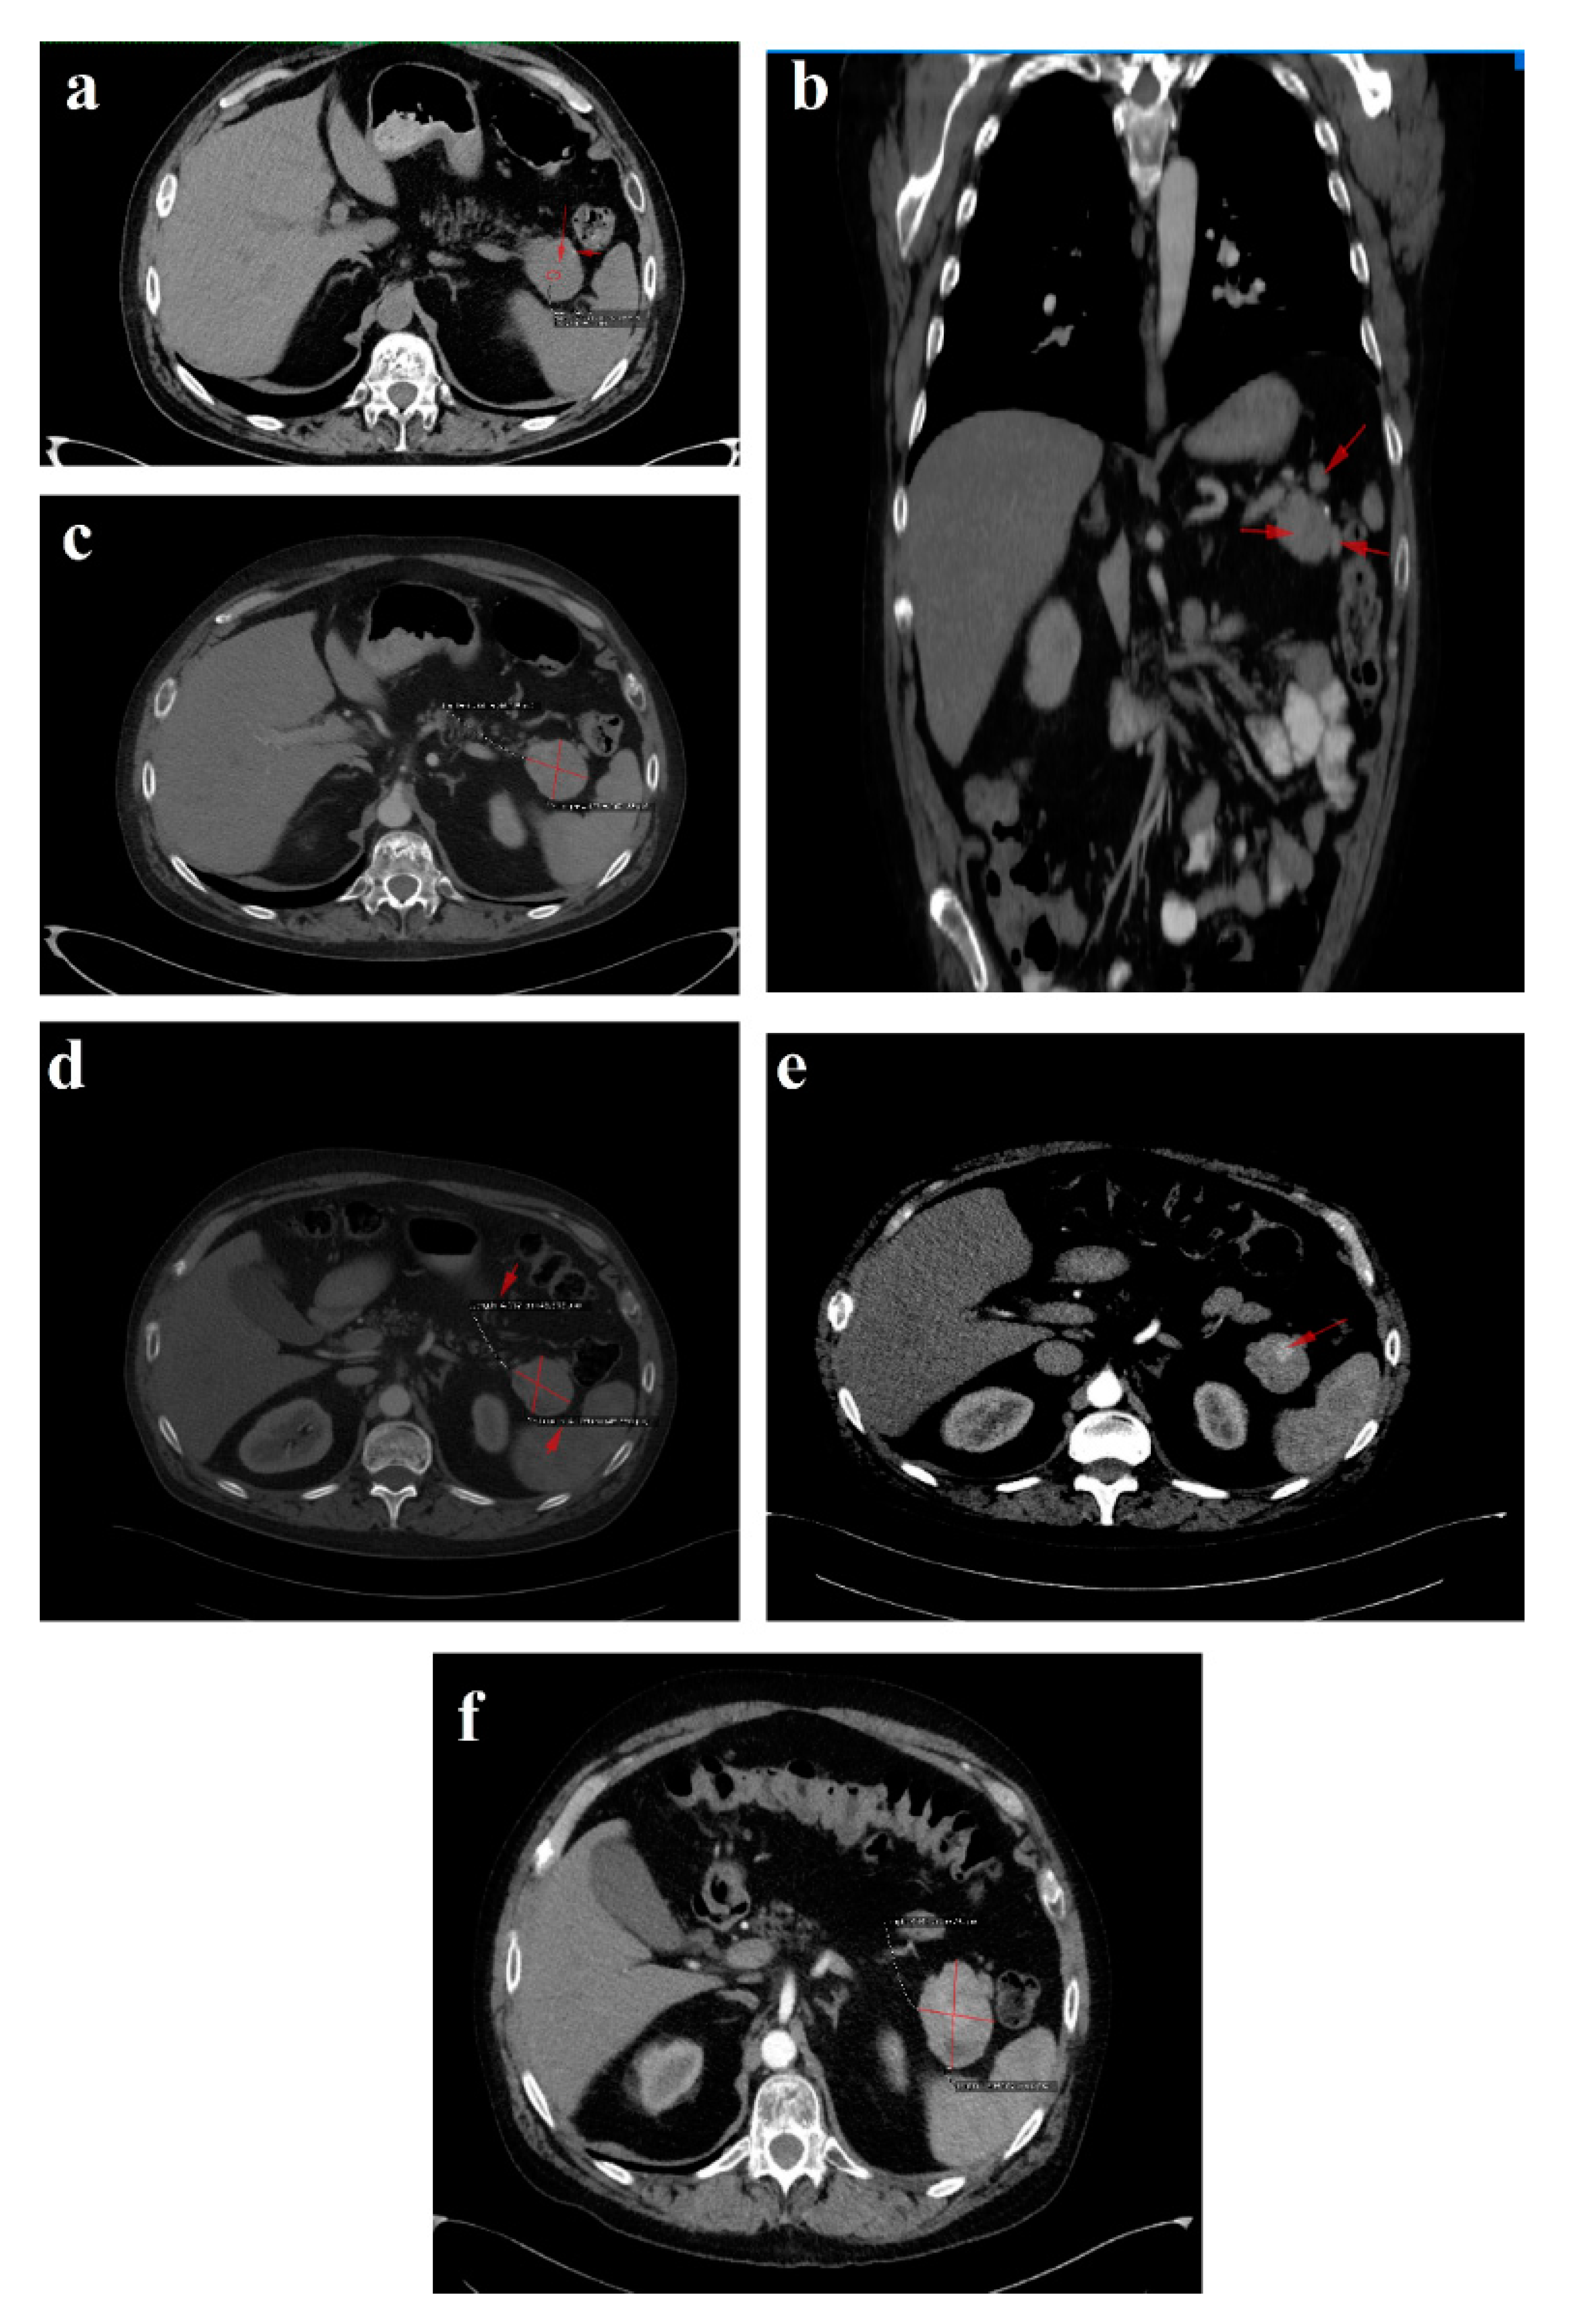

Figure 6. Follow-up CT January 2021: (a) axial image-tumor progression; (b) axial venous phase with no vascular invasion; (c) coronal reconstruction venous phase, shows the fat plan between the mass and the vascular structures, indicating that the lesion is operable. Follow-up CT April 2021: (df) venous phase sagittal, coronal and axial reconstructions, respectively, showing fluid collection after the surgical removal of the pancreatic masses and the spleen. Red arrows and line indicate the lesions described in the figure legend; further information may be redundant.

In January 2021, a follow-up CT reconfirmed locoregional tumor progression without apparent distal metastasis (Figure 6a–c), and a distal pancreatectomy and splenectomy were performed with a favorable outcome. An open approach with a bilateral subcostal incision was chosen. After opening the abdomen, a thorough examination of the peritoneal cavity was performed. We discovered a 6/5 cm tumor in the tail of the pancreas, without any vascular or retroperitoneal involvement. No liver or peritoneal metastases were present. We opted for a distal spleno-pancreatectomy in a standard fashion with a clockwise approach and individual splenic artery and vein ligation, ensuring a proper oncological safety margin on the pancreatic body. The pancreas was transected using monopolar cautery (Figure 7a) with pancreatic duct identification and clipping (Figure 7b), and the pancreatic stump was double sutured: the first was an overlapping horizontal mattress suture, and the second was a figure-eight suture (Figure 7c). Two drainage tubes were placed, the abdomen was closed, and the specimen was sent for pathology examination (Figure 7d). The postoperative course was uneventful. We checked the amylase level in the drained fluid on the third postoperative day and it was normal, which allowed us to exclude the pancreatic fistula. The abdominal ultrasonography performed did not show any collections, and the drainage tubes were removed. The patient was discharged on the eighth postoperative day.

The 3-month postoperative CgA, pancreatic polypeptide and glucagon plasma levels (193 ng/L) were normal. A follow-up CT revealed a few millimetric calcifications in the right lobe of an otherwise homogenous liver and a 105/53/48 mm fluid-filled encapsulated collection in the spleno-pancreatic space with contrast enhanced thin walls and surrounding surgical clips. Up to 40% of patients have fluid collections after distal pancreatectomy as a result of a small pancreatic leak, yet they usually are without clinical significance and very few of them will require percutaneous drainage. Since the patient was symptom-free, we decided to wait for a spontaneous resolution of the collection. No local tumor recurrence was detected. There was a slight enlargement of the lymph nodes in the perihilar hepatic region, a 15/13 mm portocaval adenopathy and an 8/7 mm newly-appeared nodule on the fissure of the round hepatic ligament (Figure 6d–f). Our MDT decided to resume SSA therapy and follow-up with the patient at 6 months.